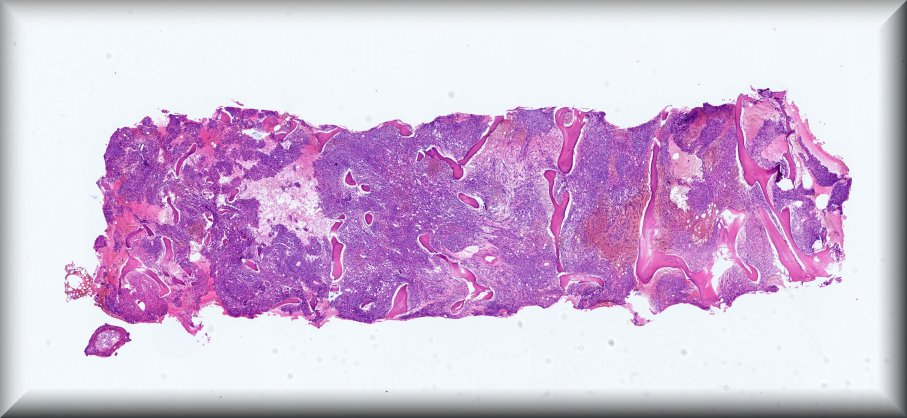

Caso 6.- Carmen Rodríguez García, Judith González López, Soraya Hernández Girón, Leticia Gómez de Manuel, Nuria Rausell Fontestad, Empar Mayordomo Aranda.

Hospital Universitario y Politécnico La Fe. Valencia

Varón de 86 años, con antedecentes de HTA, cardiopatía isquémica y DM2 en tratamiento con insulina. Diagnosticado de psoriasis hace cuatro años, actualmente en tratamiento con acitretina tópica. Es remitido por su médico de atención primaria a consultas de Hematología por anemia y linfocitosis de meses de evolución, sin clínica constitucional ni otros síntomas asociados. A nivel analítico, destaca anemia (9.9 g/dL), linfocitosis (10,34 x 10^3/µL), trombopenia (40 x 10^3/µL) y elevación de la LDH (414) como hallazgos más relevantes. En el frotis de sangre periférica se observa un 32% de linfocitos de pequeño tamaño. En el TAC toraco-abdomino-pélvico no se evidencian crecimientos adenopáticos patológicos. Se realiza aspirado y biopsia de M.O para descartar patología hematológica subyacente.